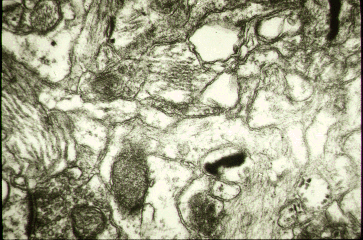

Pathology Images